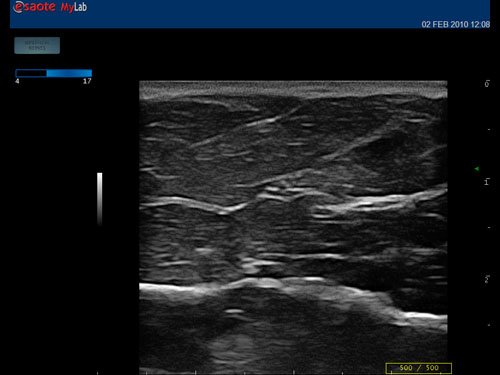

Das MyLab™One steht für das revolutionäre „Arm-held“ Hochleistungs-Ultraschallsystem mit 12”-Full-Touchscreen. Aufgrund seines geringen Gewichts und der Tragbarkeit kann es auch ohne Arbeitsfläche verwendet werden. Eine einzelne Person kann dieses Gerät aufgrund seiner einzigartigen Funktionen allein und selbstständig bedienen.

Das Ultraschallsystem MyLab™One zeigt exemplarisch den modernen Bedarf an Diagnosekapazitäten in verschiedenen Anwendungsbereichen: Radiologie, Kardiologie, Phlebologie, Frauenheilkunde, Orthopädie, Regionalanästhesie, Sportmedizin, Interventionell, Rheumatologie, Erste Hilfe, Notfallmedizin, Vaskuläre Reihenuntersuchungen, Allgemeinpraxis.

Der intuitive Touchscreen bietet dem Benutzer schnellen und einfachen Zugang zu allen Steuerungsfunktionen. Mit der beeindruckenden Bildqualität und einem kompakten Design wird MyLab™One zur idealen Ultraschalllösung am Point-of-Care.

• Breites Bild mit hoher Qualität

• Features: Farb/Doppler, Nadelführung, SW/B-Bild